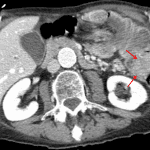

- Colo-colonic intussusception at the splenic flexure measuring 10 cm in length with a 3.5 x 2.5 cm mass at the distal margin of the intussusceptum

- Edematous appearance of the intussusceptum

- Small volume ascites around the liver extending into the right paracolic gutter and into the anatomic pelvis

- Atherosclerotic calcification of the abdominal aorta and branch vessels with fusiform ectasia of the infrarenal abdominal aorta measuring 2.5 cm in AP diameter

- Malignant colo-colonic intussusception

Colo-colonic intussusception at the splenic flexure measuring 10 cm in length with edema and possible early ischemic changes of the intussusceptum. Mass at the distal margin of the intussusceptum is concerning for a neoplastic lead point. Recommend surgical evaluation.

Small volume free intraperitoneal fluid, likely reactive to the intussusception.